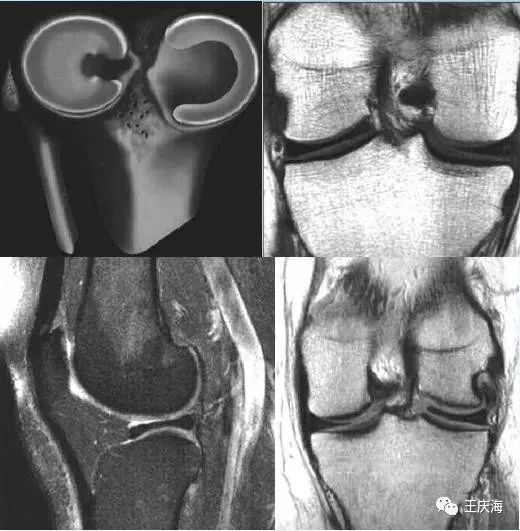

矢状面上层厚 4~5mm连续扫描 ,有 3 层或 3 层以上层面显示半月板前后角相连 ;

冠状面上半月板体部的中间层面即半月板体部最窄处的宽度>15mm或板/台比值> 20 %,即冠状位半月板最小横径与胫骨平台最大横径的比值 ;

矢状面上前后角不对称性显著增大;

冠状面像上盘状半月板中部宽度显著增宽,与同侧胫骨关节面宽度的比率(板/胫比率)超过50%,板/胫比率在51%-75%间为小盘状半月板,>75%的为大盘状半月板,有些小盘状半月板的环较小,呈小“C”或小“O”形改变。

冠状面(图A)见外侧半月板体部宽度增宽,横断面(图B)示外侧半月板环较小。

大盘状半月板覆盖75%以上的一侧胫骨平台

矢状面T2WI(上图)显示半月板覆盖整个一侧胫骨平台,形态不规则,信号不均匀。